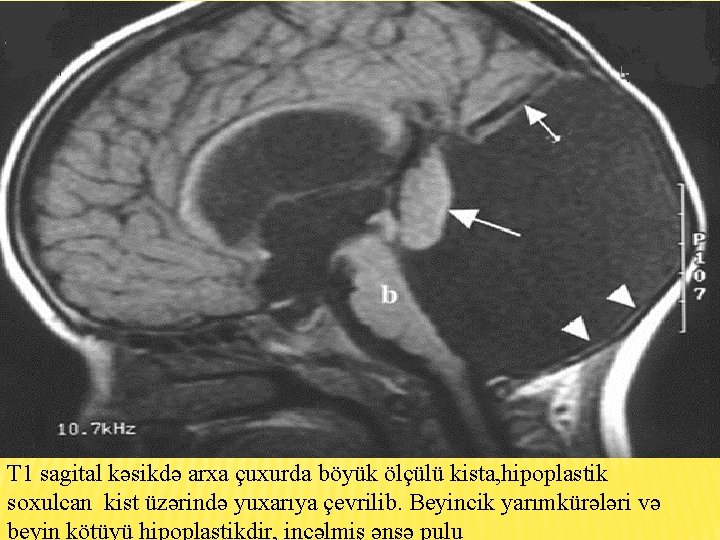

2 - ci xəstə � Qız uşağı � Yaş : 5 � Klinik əlamətlər : Hidrosefaliya, əqli inkişafdan geriqalma, hərəki aktivliyin pozulması � Diaqnoz : klassik DW

T 1 sagital kəsikdə arxa çuxurda böyük ölçülü kista, hipoplastik soxulcan kist üzərində yuxarıya çevrilib. Beyincik yarımkürələri və beyin kötüyü hipoplastikdir, incəlmiş ənsə pulu

T 2 şəkildə hidrosefaliya, arxa çuxurda böyük BOM kistası incəlmiş ənsə sümüyü və hipoplastik beyincik yarımkürələri qanad şəkilli

T 1 aksiyal kəsikdə yan mədəciklərin böyüməsi , arxada kista